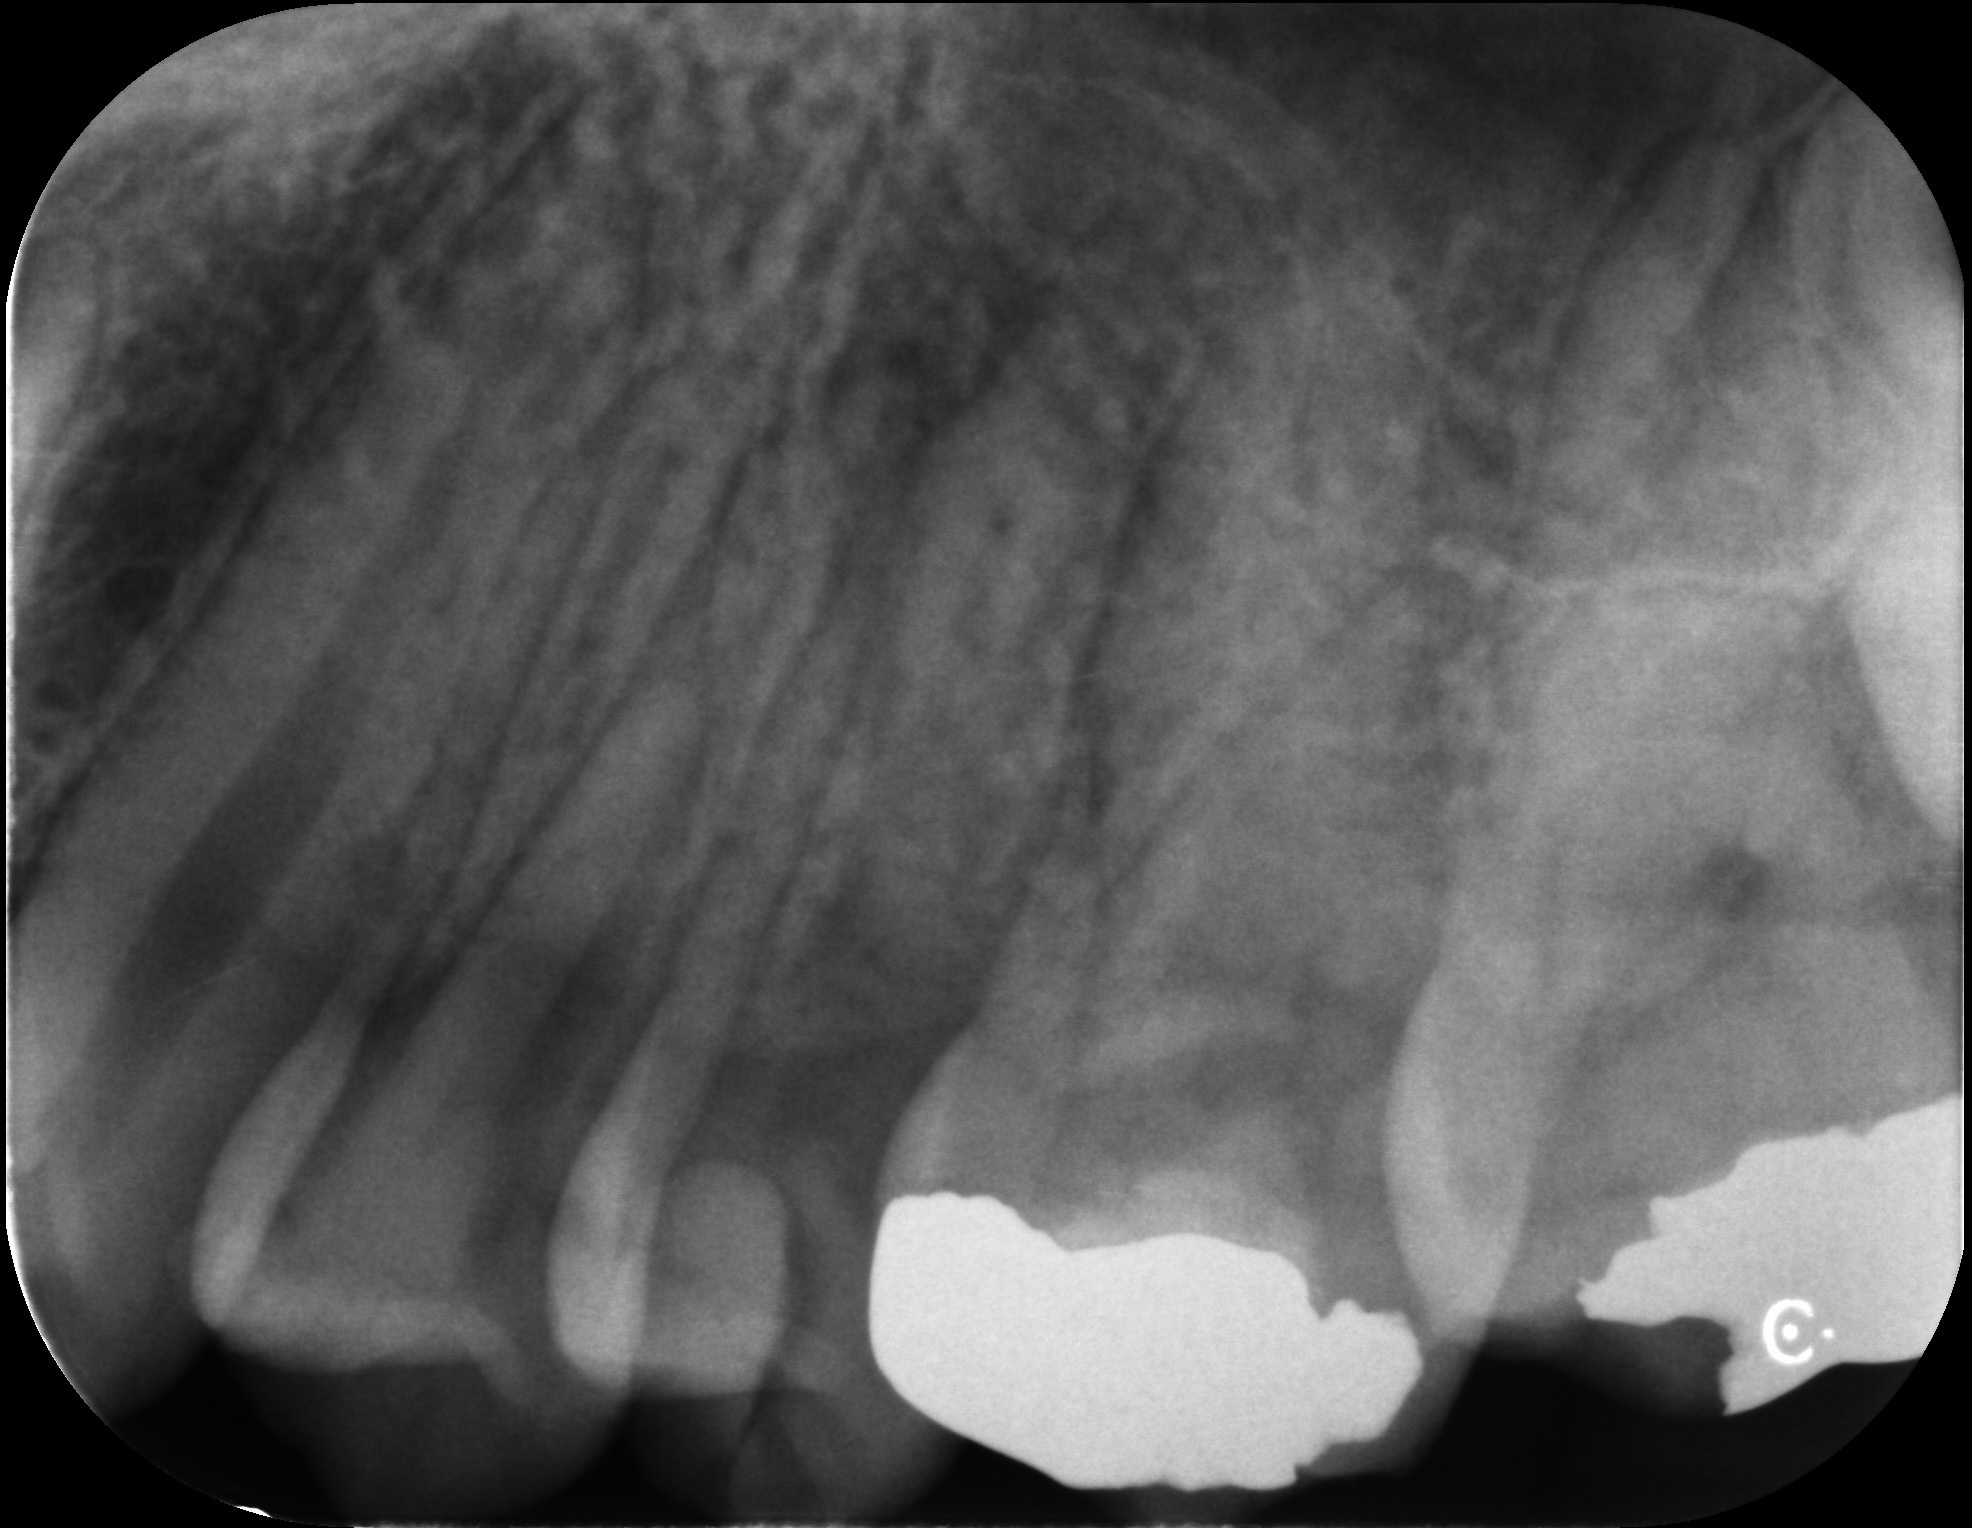

根尖性歯周炎の歯を

再根管治療によって歯を残した症例

タップで写真の拡大ができます。

Before

After

Under Treatment

主訴

抜歯が必要と言われた歯の精査を希望

診断

根尖性歯周炎(根尖吸収、ストリップパーフォレーションを伴う)

治療方針

重度の感染および根管内の損傷が認められる難症例であったが、 歯質の残存量および歯周組織の状態から保存可能と判断した。

歯根破折を疑う所見も認められなかったため、 患者の希望も踏まえ、保存的に再根管治療を行う方針とした。

治療内容

リトリートメント(大臼歯)、MTAセメントによる封鎖、レジンコア

治療期間

約1ヶ月

治療費用

220,000

結果

初診時には根管内に肉芽組織および排膿を認めたが、 感染コントロール後に炎症所見は消失した。

その後MTAセメントにて封鎖を行い、 術後症状は認めず、根尖病変は縮小傾向を示している。

治療の

リスク

根尖病変が完全に消失しない可能性

考察

複数回の根管治療既往があり、根管内は複雑な状態であったが、 適切な感染源の除去と封鎖により良好な経過が得られている。

難症例においては、保存の可否を適切に判断した上で、 精密な処置を行うことが重要である。